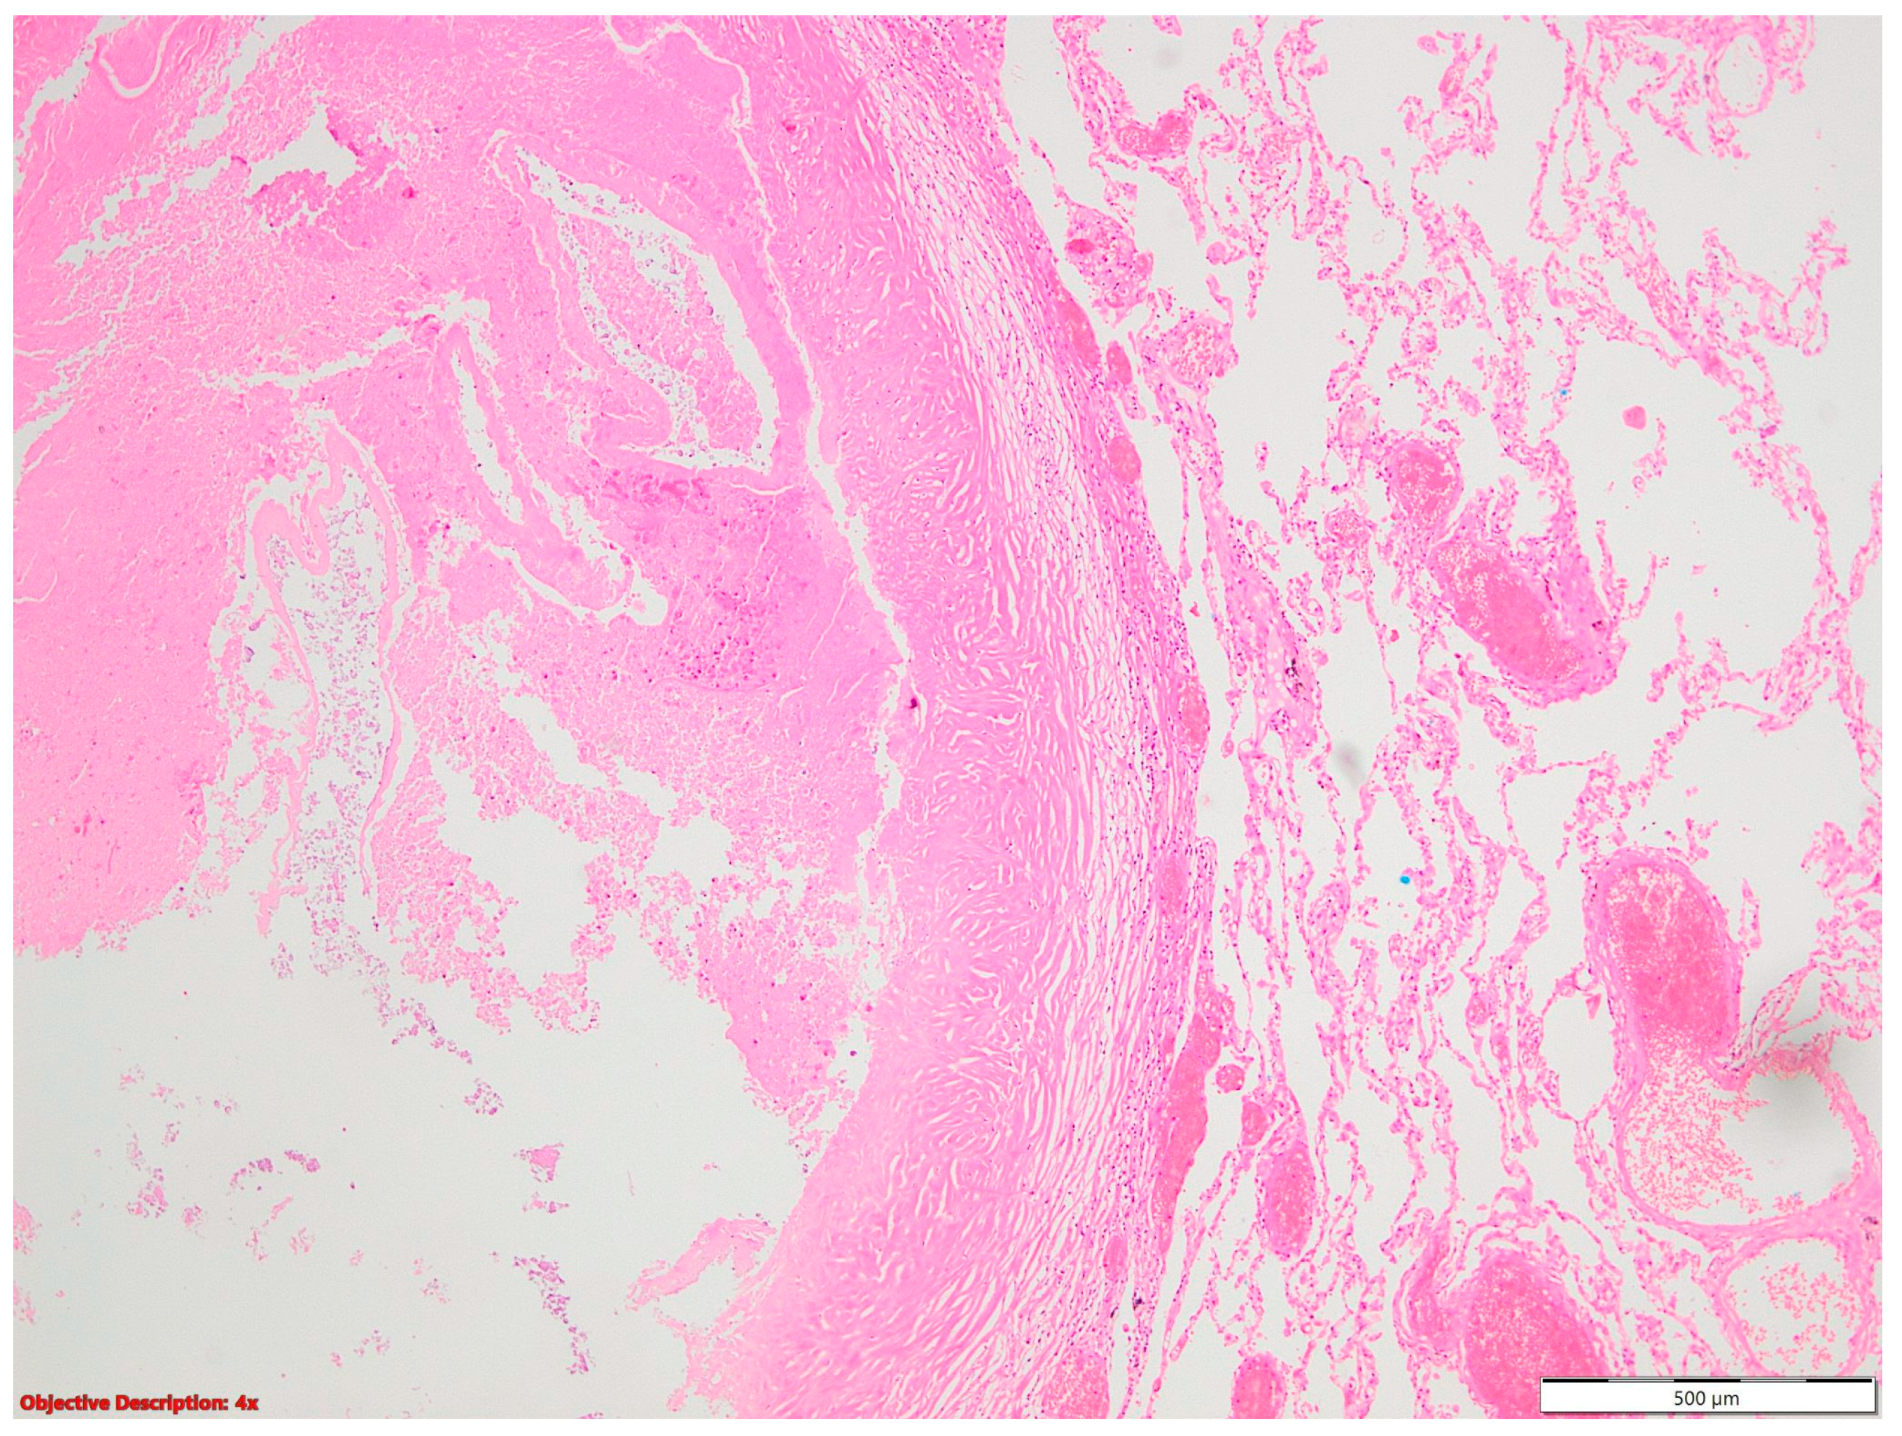

Regarding the high prevalence of Mycobacterium tuberculosis in our country [2,7], all or part of the fibronodular lesions of the lung parenchyma (Figure 4), nodular calcification, and osseous/osteomedullary metaplasia (Figure 5) could represent sequelae of tuberculosis.

Figure 4. Fibronodular lesion (left side) in the lung parenchyma (right side); HE, 40×.